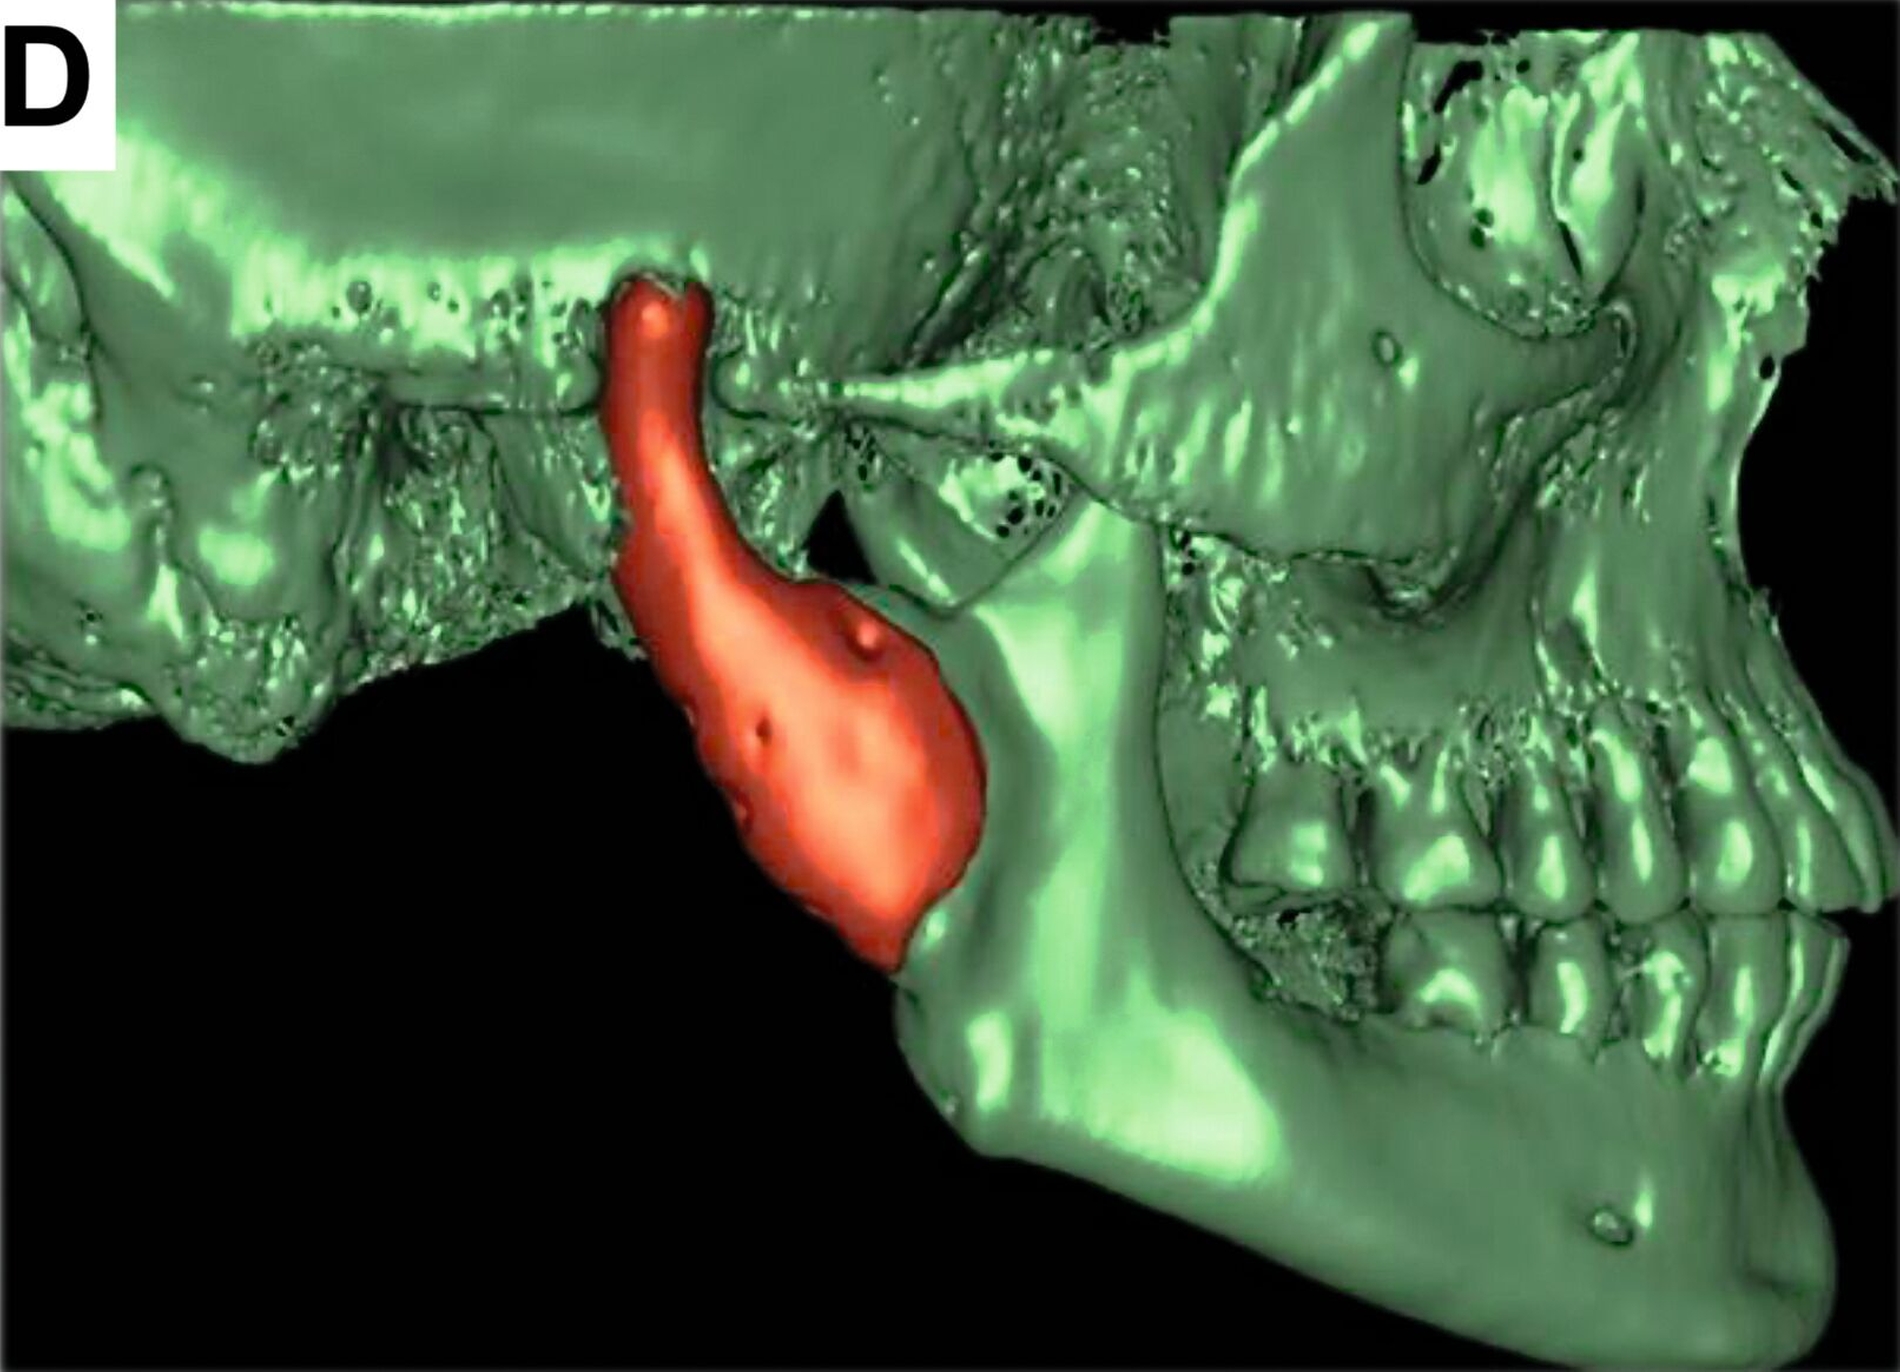

Nach einer achtmonatigen Konsolidierungsphase unter Verwendung einer Okklusionsschiene wurde zur Planung einer industriell gefertigten CAD/CAM-Kiefergelenk-Totalendoprothese ein Dünnschicht-CT durchgeführt (Abbildung 3).

Die finale patientenspezifische CAD/CAM-Kiefergelenkendoprothese wurde von der Firma Materialise in Löwen, Belgien, hergestellt. Vier Monate nach der Explantation konnte die Patientin erfolgreich mit Ersatz von Kondylus und Fossa mandibularis versorgt werden (Abbildung 4).